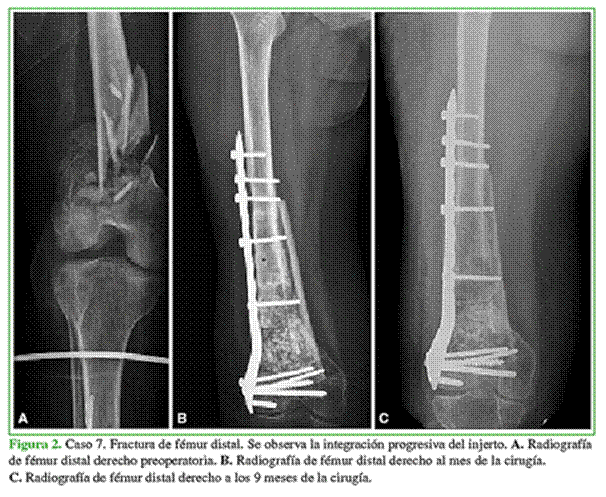

De acuerdo con los estudios radiográficos, ninguno tenía signos de infección del injerto o del sitio quirúrgico ni aflojamiento del material de osteosíntesis (Tablas 3 y 4, Figuras 1 y 2).

Se corroboró la correcta alineación del injerto en todos los casos. Así mismo, según la Escala de Osteointegración del ISOLS, la integración fue excelente en el 54% de los pacientes (7 casos), buena en el 23% (3 pacientes), aceptable en el 8% (1 caso) y pobre en el 15% (2 casos). En la Tabla 5, se detallan los resultados de cada paciente para la integración del injerto de acuerdo con la escala mencionada.